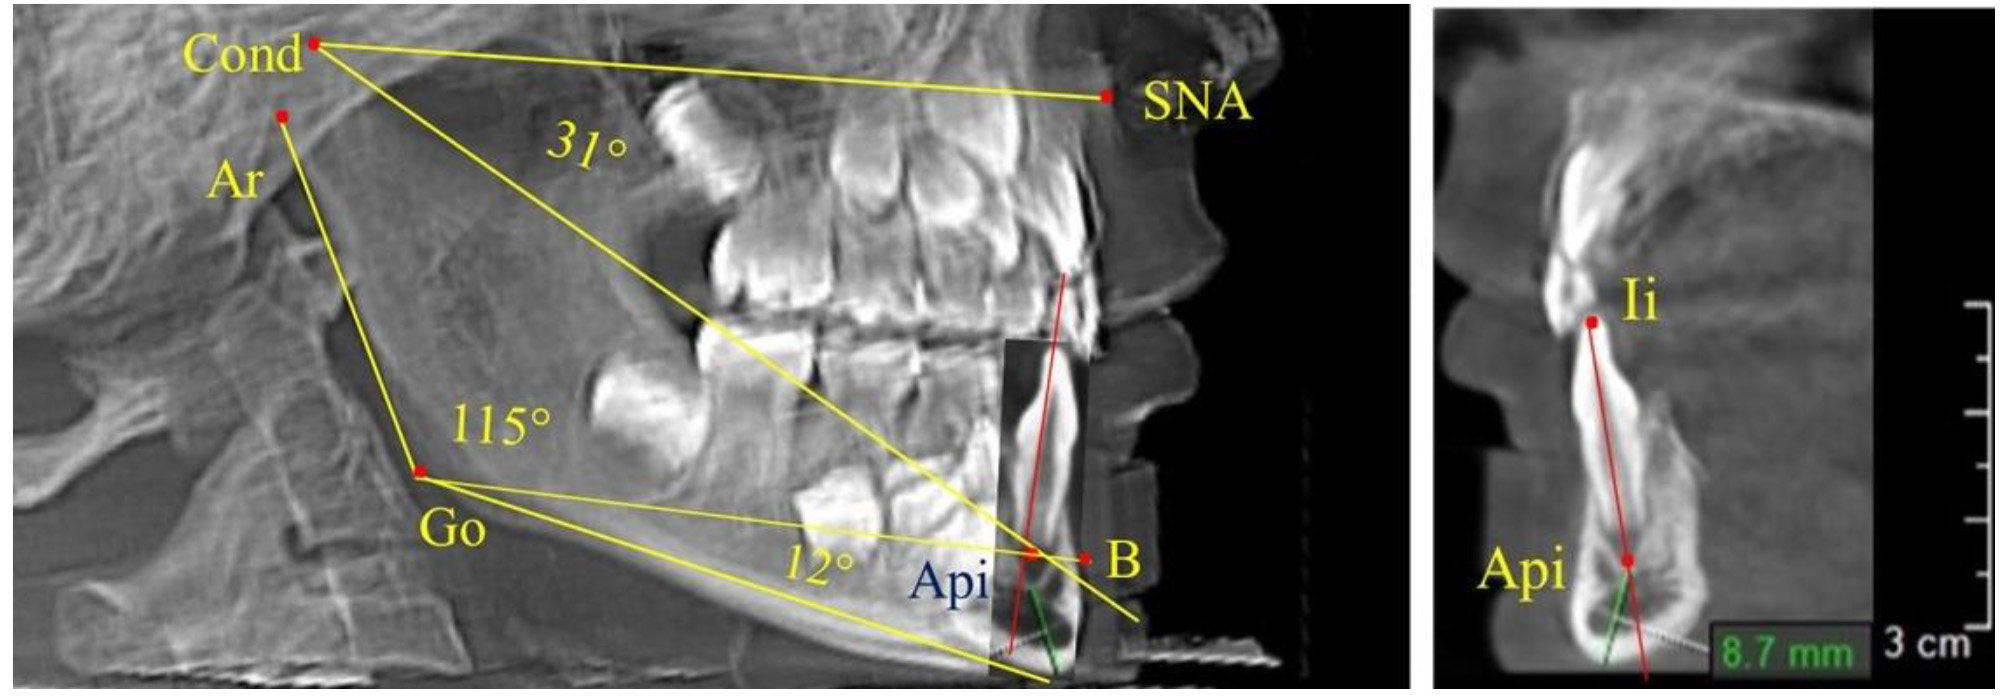

При анализе 16 рентгенограмм с аномалиями окклюзии в вертикальном направлении были выявлены признаки изменения основного гнатического угла. Так, для гнатических аномалий глубокой резцовой окклюзии/дизокклюзии (9 человек) отмечалось уменьшение угла гнатической части лица, величина которого была менее 26°. В то же время для гнатических аномалий (7 человек) вертикальной резцовой дизокклюзии («открытый» прикус) определялось увеличение угла гнатической части лица, который превышал значения в 33° (рис. 7).

Рис. 7. Варианты ТРГ при глубоком прикусе (а) и при открытом прикусе (б)

На представленных клинических примерах, несмотря на различия параметров основного угла гнатической части лица, определялись однотипные варианты угла нижней челюсти Ar-Go-Me и его составных частей Ar-Go-Api и Api-Go-Me.

Таким образом, установлено, что основным показателем, определяющим оптимальные параметры гнатического отдела лица, является угол гнатического отдела лица, образованный пересечением линии, соединяющей точку передней носовой ости с верхней точкой суставной головки SNA-Cond, и линией, отходящей от суставной точки до верхушки корня нижнего медиального резца Cond-Api. Средняя величина угла гнатического отдела SNA-Cond-Api составляла (29,96 ± 0,84)° при физиологической окклюзии постоянных зубов и практически была аналогичной во все периоды онтогенеза.